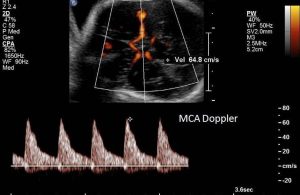

فحص دوبلر للشريان الدماغي الأوسط: إذا تم اكتشاف بعض المشاكل أثناء فحص دوبلر للشريان السري ، يتم إجراء فحص دوبلر للشريان لفحص تدفق الدم في دماغ الطفل.

يعتمد التوقيت الأمثل للولادة في الأجنة المصابة بتشوهات دوبلر وتأخر النمو داخل الرحم على السبب الأساسي وعمر الحمل المقدر. بالإضافة إلى الشرايين السرية ، يمكننا تقييم الشريان الدماغي الأوسط في الدماغ لتقييم ما إذا كان الجنين يحاول حماية الدماغ في وسط بيئة فقيرة بالأكسجين. أكتوبر.